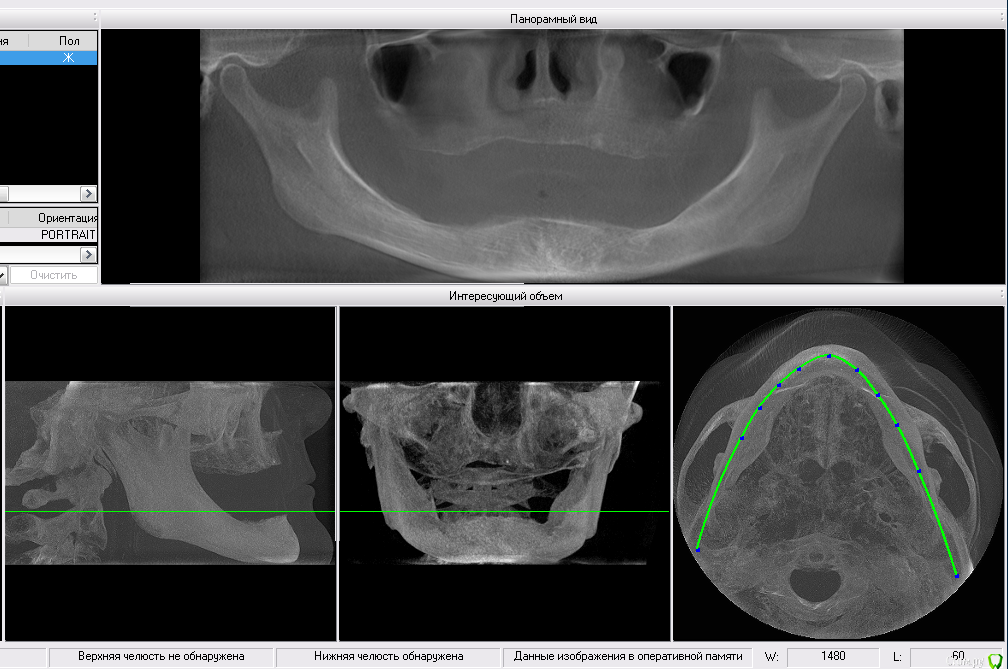

Татьяна Luckyman Опубликовано 21 июня, 2017 Поделиться Опубликовано 21 июня, 2017 Здравствуйте! Заранее извиняюсь, если будет неверная терминология, все описание со слов мамы.Итак, она около 10 лет ходит со съемными протезами (своих зубов не осталось вообще), очень сильно съеден низ, десна тонкая и атрофированная. По словам врача нужно как можно быстрее ставить импланты, иначе в ближайший год мама может остаться вообще без зубов, ибо не на что будет ставить.В одной клинике советуют ставить хотя бы низ, но лучше сразу и верх, по 4 импланта, мост, балку, ценник примерно 400 тысяч за верх и низ, если только низ 206, кажется.В другом месте предлагают делать пока только низ: всего 2 импланта, также балку, ценник 150 тысяч. Вопросы такие: 1. Как делать лучше? Есть ли еще варианты, которые помогут сохранить зубы?2. Сколько в действительности еще есть времени на раздумья, подготовку и, в конце концов, накопление средств?3. Выделяются ли квоты на такие операции? Хотелось бы сделать сразу и верх и низ, часть суммы накоплена, но вряд ли остальное успеем собрать за полгода.4. Импланты чьего производства лучше ставить, а на какие вообще не соглашаться? Ссылка на комментарий

red_butler Опубликовано 21 июня, 2017 Поделиться Опубликовано 21 июня, 2017 1. Как делать лучше? Лучше не бывает, каждый вариант имеет плюсы и минусы. Есть ли еще варианты, которые помогут сохранить зубы? о каких зубах речь??? На снимках зубы отсутствуют 4. Импланты чьего производства лучше ставить, а на какие вообще не соглашаться? Ищите врача, а не импланты. Ссылка на комментарий